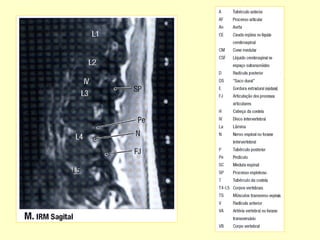

PADRÃO ‘ OURO’ PARA AVALIAR A

COLUNA POR MÉTODO DE IMAGEM

É A RESSONÂNCIA MAGNÉTICA.

12ª SEMANA- MEDULA ESPINHAL E

CANAL VERTEBRAL QUASE IGUAIS.

EVOLUTIVAMENTE O CANAL SE

TORNA MAIOR , DE MODO QUE

OS NERVOS ESPINHAIS TEM UM

CURSO MAIS LONGO PARA ALCANÇAR

O NÍVEL CORRETO.CAUDA EQUINA.

CONE MEDULAR NÍVEL L1-L2 .

6- RESSONÂNCIA MAGNÉTICA.